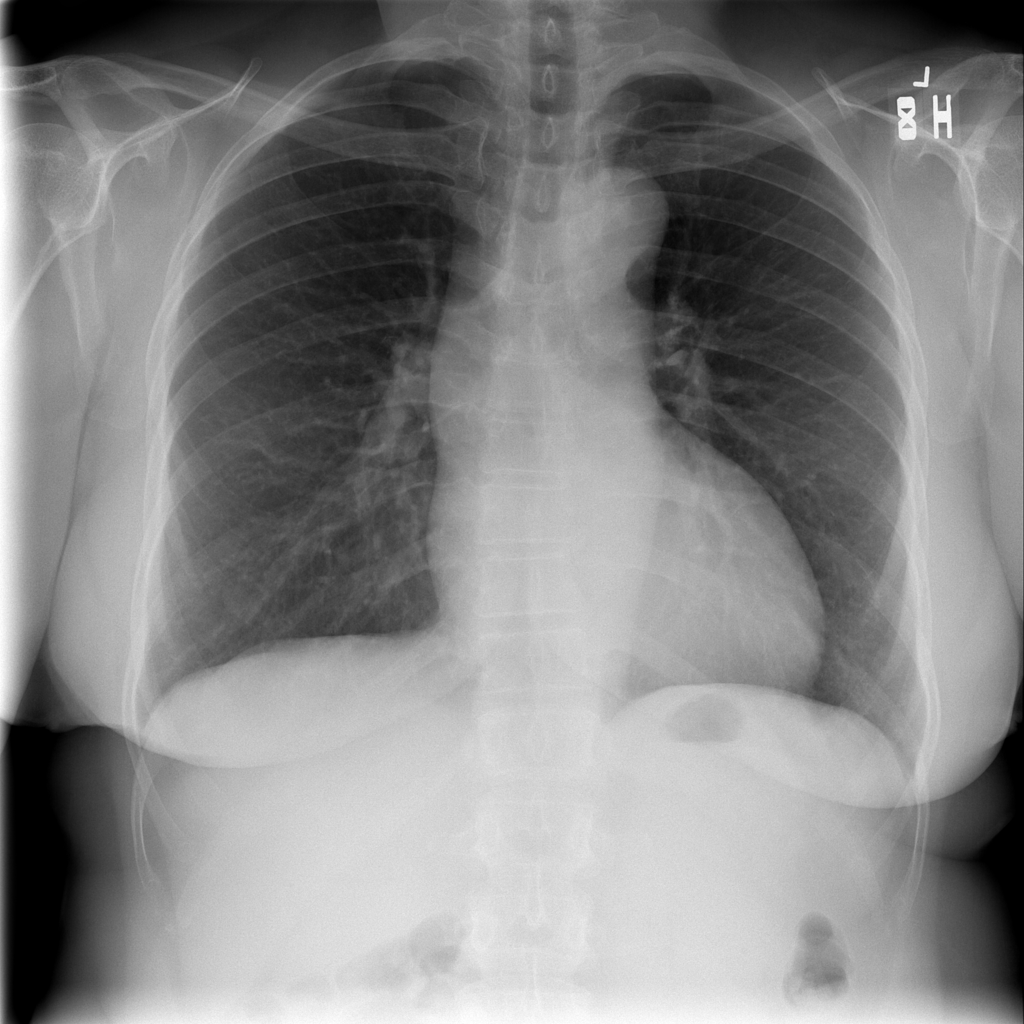

PAT-AE5C · IMG-000Cardiomegaly

PAT-AE5C · IMG-000

PA